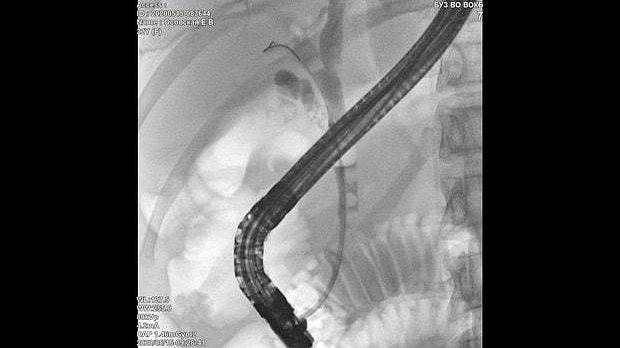

Здравствуйте. Пациентка, 32 года. Поступила на хирургическое отделение с диагнозом ЖКБ: холедохолитиаз. По данным МРТ: ЖКБ, множественные мелкие конкременты холедоха. При дуоденоскопии выявлено наличие вклиненного конкремента большого дуоденального сосочка. Выполнена прекатсфинктеротомия, получено 3 конкремента, диаметром около 0.4-0.5 см. Далее канюляция холедоха проволочным папиллотомом, выявлены многочисленные конкременты холедоха. Выполнена литоэкстракция ревизионным баллоном (на последнем фото окклюзионная холангиография - в просвете холедоха не конкременты, а пузырьки воздуха)).